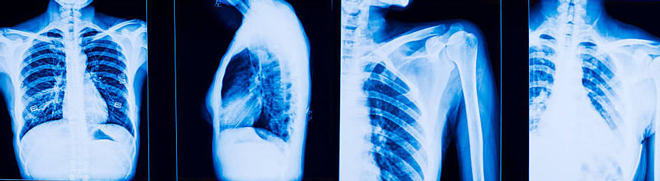

Виды флюорографии

Видов рентгенологического обследования с помощью флюорографа существует 3 – пленочная, цифровая флюорография, сканирование в цифровом виде. Разделение методик напрямую связано с оборудованием, которое применяется в медицинской практике для проведения процедуры. Чем качественнее аппарат, тем выше эффективность и точность диагностического мероприятия. Описание современных методов флюорографии:

Флюорография позволяет выявить различные патологические изменения в легочной ткани.

Несмотря на то, что между рентгенографией и флюорографией есть немало отличий, эти методы исследования относятся к одному виду лучевой диагностики с использованием рентгеновского излучения. В то же время это далеко не одно и то же, так как флюорография и рентген легких используются в разных ситуациях:

Флюорография представляет собой разновидность рентгенологического обследования, но все же между этими исследованиями есть разница.